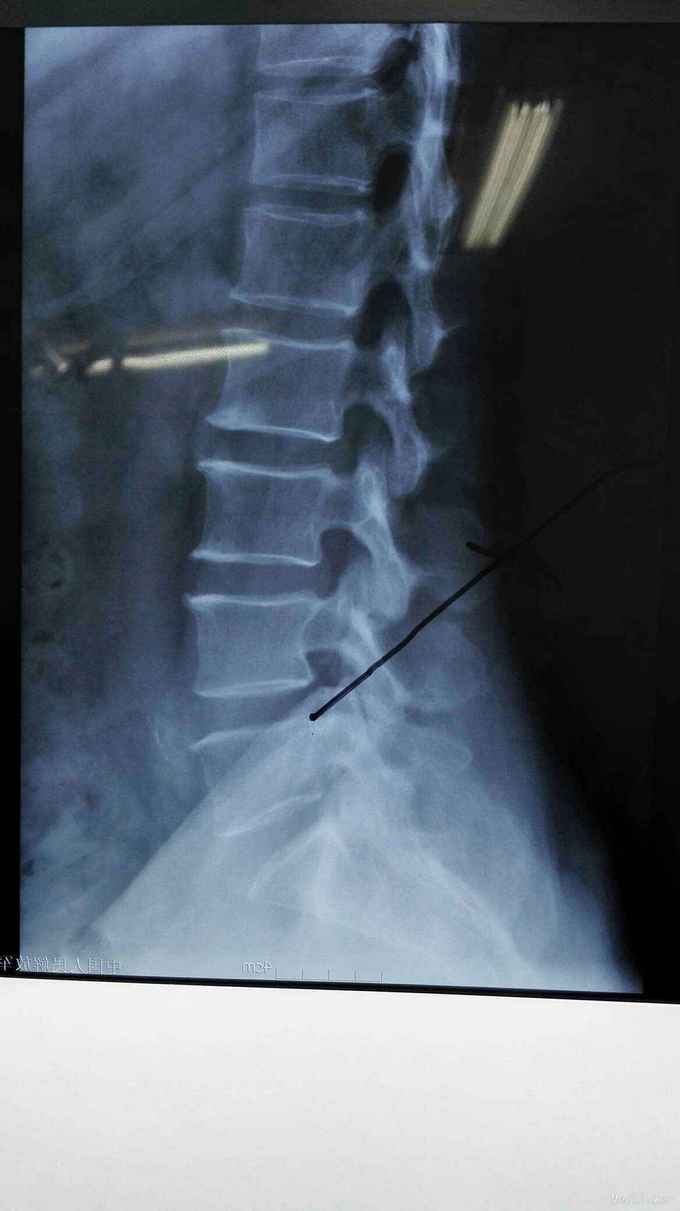

患者左下肢疼痛麻木1年余,间隙性跛行明显。

查体符合腰5神经根受压体征。腰椎CT、MRI提示腰4/5椎间盘突出,椎管狭窄。

考虑腰椎间盘突出伴椎管狭窄症。行椎间孔镜下髓核摘除,椎间孔成形。